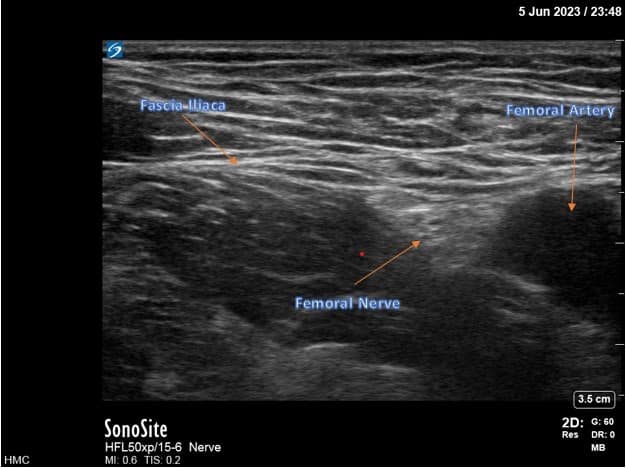

For femoral nerve lead placement, the patient is placed in the supine position. The ultrasound probe is placed transversely at the inguinal crease over the femoral artery. An in-plane technique is used for needle insertion (Figure 3). The skin and muscle are first infiltrated with 1% lidocaine, ensuring that the local anesthetic is not injected close to the nerves as this may interfere with stimulation testing. The percutaneous sleeve containing the stimulating probe is advanced towards the femoral nerve (Figure 4).